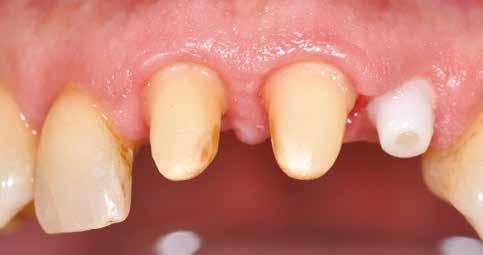

Esetismertetés

Az 50 éves nőpáciens az alsó és felső állcsont területén egyaránt panaszt (fájdalom, ráharapási érzékenység) okozó, harmadfokban mozgatható fogak miatt jelentkezett rendelőnkben. Az általános anamnézisben említést érdemlő betegség, műtét nem szerepelt. Az elvégzett klinikai és radiológiai vizsgálatok (1–2. ábra) alapján fogai reménytelen parodontális státusúnak bizonyultak, hosszú távon sem megtartásuk, sem protetikai célú felhasználásuk nem volt lehetséges. A parodontális prognózis a fogak eltávolításának abszolút indikációját jelentette. Ezáltal mindkét állcsontban teljes foghiány kialakulásával kellett számolnunk. A protetikai szemléletű, „visszafelé” tervezés elveit követtük a hosszú távú funkcionális, esztétikai siker és szöveti stabilitás elérése érdekében: mindkét állcsontban overdenture típusú fogpótlás készítése mellett döntöttünk. A megfelelő implant-protetikai rehabilitáció alapja az implantátumok megfelelő pozicionálása. A korábbi parodontális kórfolyamat következtében a processus alveolarisokat érintő eredendő csontdeficittel kellett számolnunk, amelyet tovább súlyosbíthatott volna a hagyományos extrakciós technikát követő involúciós atrófia. Ezért a páciens kivizsgálása és megfelelő előkészítése után a fog eltávolításával egy időben PRF

27 VI. ÉVFOLYAM – 2023. 4. SZÁM

Sticky Tooth segítségével kivitelezett alveolus prezerváció mellett döntöttünk, a megfelelő csontos és mukogingivális gyógyulás minőségi és mennyiségi elősegítése érdekében. A PRF készítmény mennyiségét, minőségét, kezelhetőségét és hatékonyságát jelentősen befolyásolják a páciens laborértékei, ezért kezelési protokollunk szerint a műtétet megelőzően minden esetben laborvizsgálatot végzünk (hemoglobin: 134 g/liter, hematokrit: 0,43, fehérvérsejt: 6,6 G/liter, CRP: 13,60 mg/liter, vércukor: 6,2 mmol/liter, összkoleszterin: 7,00 mmol/liter, triglicerid: 1,08 mmol/liter, HDL koleszterin 2,57 mmol/liter, LDL koleszterin 1,12 mmol/liter), D3 vitamin: 117,5 nmol/liter).

A fogak eltávolítása és az alveoláris csont megőrzésének és regenerációjának segítése céljából elvégzett augmentáció altatásban történt. Óvatos, atraumatikus extrakciót követően eltávolítottuk a parodontális és periapikális gyulladásos folyamatok eredményeként jelen lévő sarjszövetet. A bukkális csontfal hiánya és a tervezett vertikális augmentáció miatt indokolt membrántechnika megfelelő kivitelezése céljából a felső állcsonton mukoperioszteális lebenyt képeztünk (3–4. ábra). Az alveolus prezervációt Sticky Tooth, PRF és titánerősítésű teflon (PTFE-Ti) membránok segítségével végeztük el, a J. Choukroun által megadott vérvételi és centrifugálási protokoll (28) elveinek betartásával: kizárólag Process for PRF Duo Quattro System eszközöket, centrifugát, vérvételi egységet és csöveket, a membránok előállításához PRF Boxot használtunk. Az A-PRF és S-PRF csöveket a PomPac eljárásnak megfelelően 4 Celsius-fokra előhűtöttük. Az eltávolított fogak makroszkópos tisztítását és darabolását nagy fordulattal (300 000 RPM) fogászati turbinába helyezett gyémántfúróval végeztük, majd Tooth Transformer™ berendezéssel, annak gyári reagens rendszerével kezelt őrleményt nyertünk. A Sticky Tooth készítmény előállítása a PRF készítmény és az őrlemény